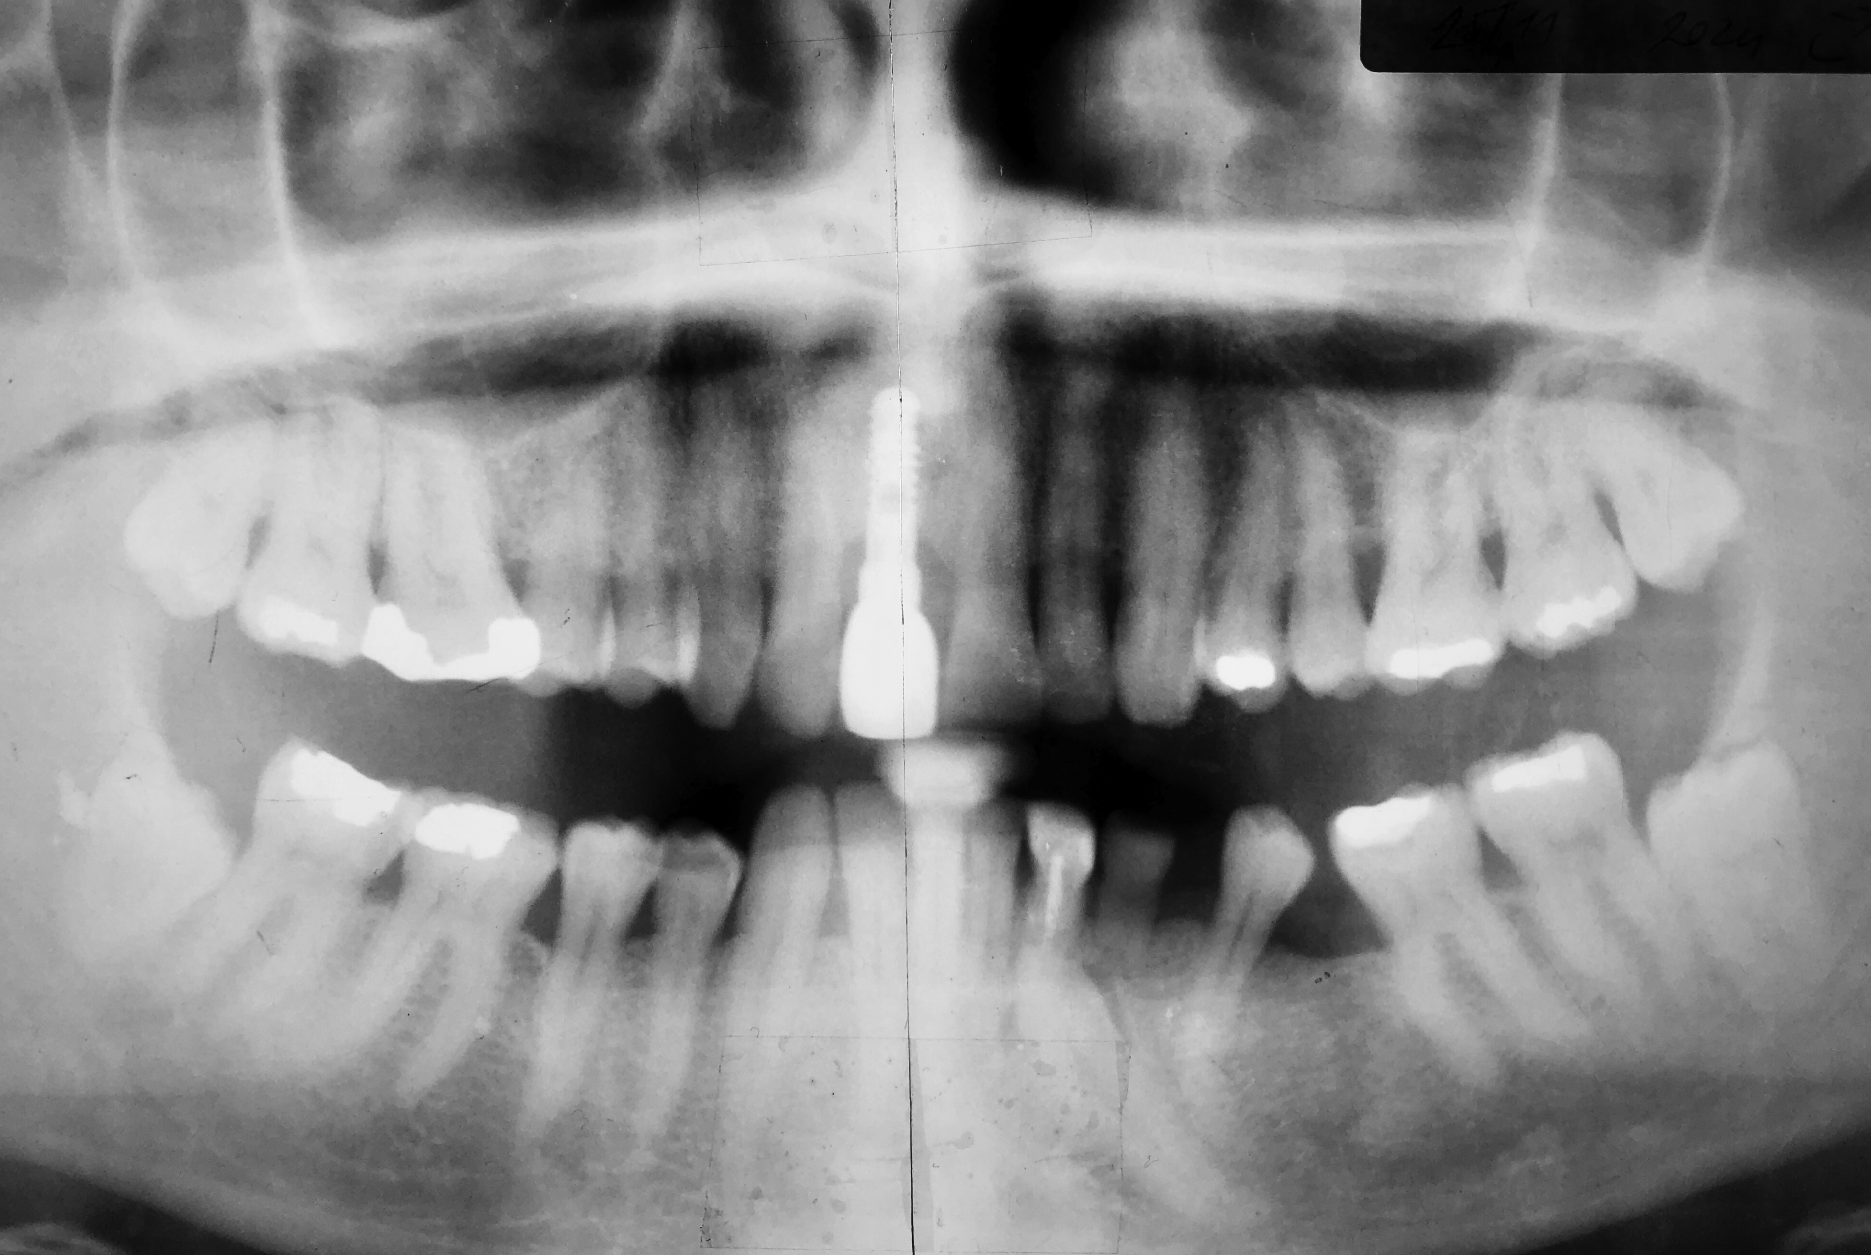

Die letzte Röntgenaufnahme vom November 2024. Das Implantat ist 23 Jahre in Funktion. Auch trotz des signifikanten Bruxismus ist der ursprüngliche Zahnersatz funktionsfähig und ästhetisch zufriedenstellend.